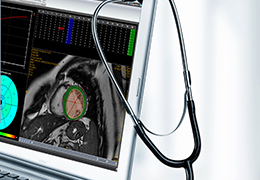

View X-Ray CT & MRI Scans Fast and Easily

FREE and easy to use 3D DICOM Viewer – for surgeons and patient education

Designed for surgeons, Pro Surgical 3D makes it easy to view patient scans quickly. Pro Surgical 3D facilitates the optimal 3D treatment and assessment workflows based on X-ray CT and MRI scans – and best of all, it’s FREE!

Everyone – including surgeons, patients and their loved ones – benefits from being better informed by the wealth of information buried within CT and MRI scans. Pro Surgical 3D gives surgeons more information to develop optimal treatment plans for patients. It also helps patients and their support group better understand their medical condition and proposed treatment options.